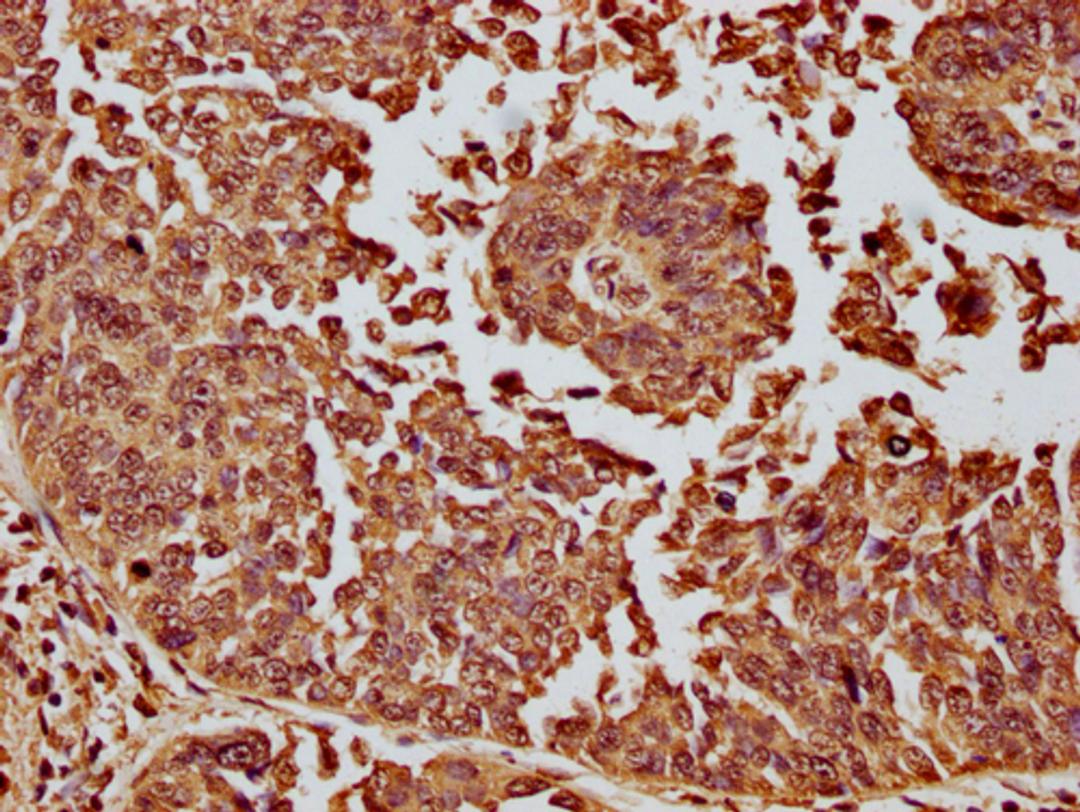

IHC image of CSB-PA010087OA11nme1HU diluted at 1:10 and staining in paraffin-embedded human cervical cancer performed on a Leica BondTM system. After dewaxing and hydration, antigen retrieval was mediated by high pressure in a citrate buffer (pH 6.0). Section was blocked with 10% normal goat serum 30min at RT. Then primary antibody (1% BSA) was incubated at 4°C overnight. The primary is detected by a biotinylated secondary antibody and visualized using an HRP conjugated SP system.